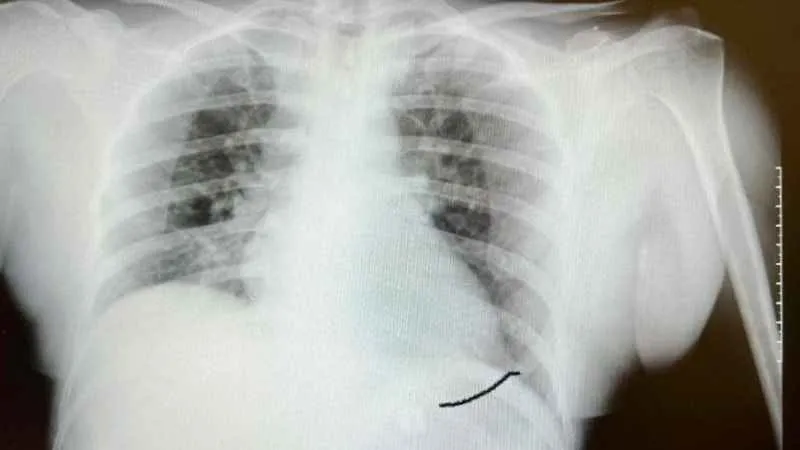

“O hastanede beyin ve sinir cerrahisi uzmanı tarafından ameliyata alınan Sultan Tıraş’ın boyun omuruna konulan iki aparattan biri çıkarılmış, ancak diğerinin yemek borusunu delip mideye indiği belirlenmiş. İlgili hekim bana ulaşarak bilgilendirmeyi yaptı ve hastayı hastanemize sevk etti. Yoğun bakıma alınan hastaya yaptığımız detaylı tetkikler ve klinik değerlendirme sonucu mediyastenit (ciddi göğüs enfeksiyonu) belirlendi. Bu ciddi bir sorun olup, hayati riski yüksektir. En hızlı şekilde tıbbi tedaviye başladık, gastroenteroloji bölümümüzde endoskopi yapıldı. Yemek borusunda oluşan delik ve delikten mideye inen metalik cerrahi aparat görüldü. Göğüs kafesi içinde ciddi bir iltihap ve hava birikimi vardı. Hasta yakınları durum ile ilgili bilgilendirildi, riskler kendileri ile paylaşılarak hastamıza tıbbi müdahale edebilmemiz gerekli onayları alındı.”

“Yaklaşık 6 saat süren bir ameliyat oldu. Hastamıza ilk endoskopik yol ile göğüs orta bölümdeki (mediasten ki bu bölgeye insan hayatının makine dairesi deriz) cerahat boşaltılıp tahliye edildi. Daha sonra boyun bölgesindeki biriken iltihap temizlendi. Yemek borundaki 2 cm’lik perforasyon (delik) tespiti ve tamiri yapıldı” diyen Prof. Dr. Elbeyli, şu bilgileri paylaştı:

Hastanın endoskopik incelemesinde yabancı cisim tespit edildi

“Endoskopi sırasında hastanın midesinde metalik bir oluşuma benzer yabancı cisim ile yemek borusunda ülser görünümü izledik. Lezyon bölgesi belirlendikten sonra hastamızın tedavisi için Göğüs Cerrahisi Bölümümüze durumu ilettik. Prof. Dr. Levent Elbeyli Hocamız hastamızın sağlığına kavuşması için gerekli tedaviyi planlayarak, başarılı bir operasyonla sonuca ulaştı. Emeği geçen herkese teşekkür ediyorum. Hastamızı sağlıklı bir ömür diliyorum.”